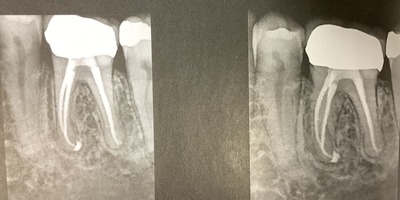

根管治療の経過

6ヶ月後のレントゲンでは根っこに影はあったが、大きくはなっていない。

12ヶ月後、歯周ポケットは2ミリ以下で出血無し。

レントゲンでは影が小さうなってきて、治ってきていた。

1年に1回の検診とし完全に治るのを確認した。

病気が治癒し、この診断と治療が正しかった事が確認された。